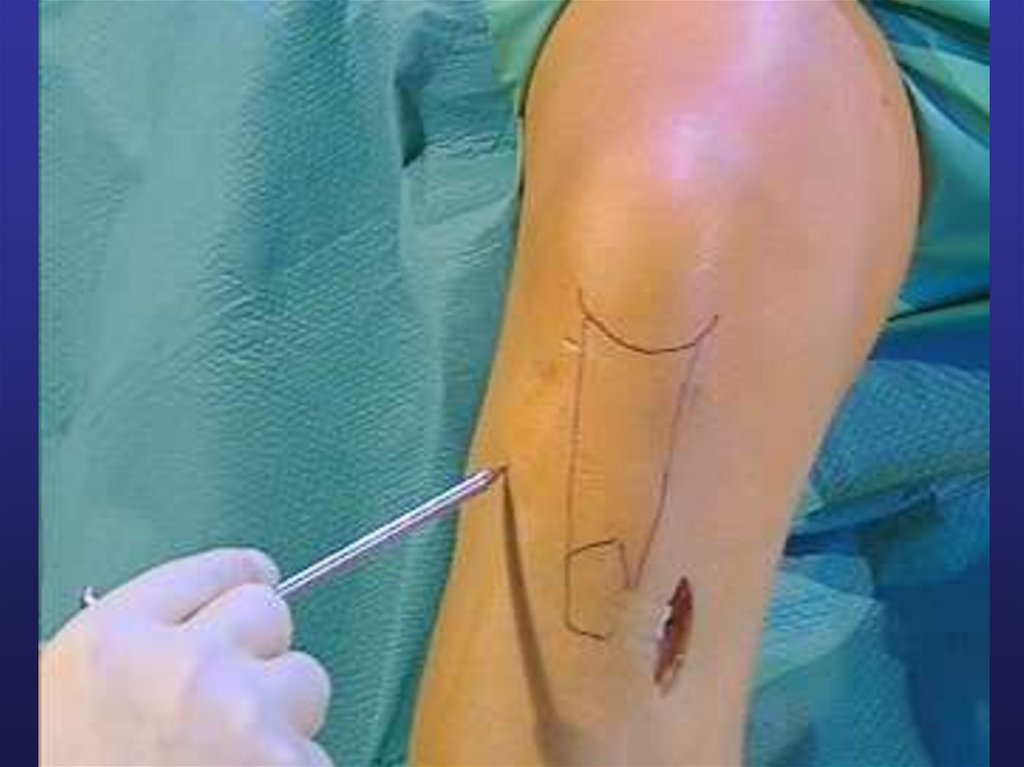

33. ПО ХАРАКТЕРУ РАНЕВОГО КАНАЛА